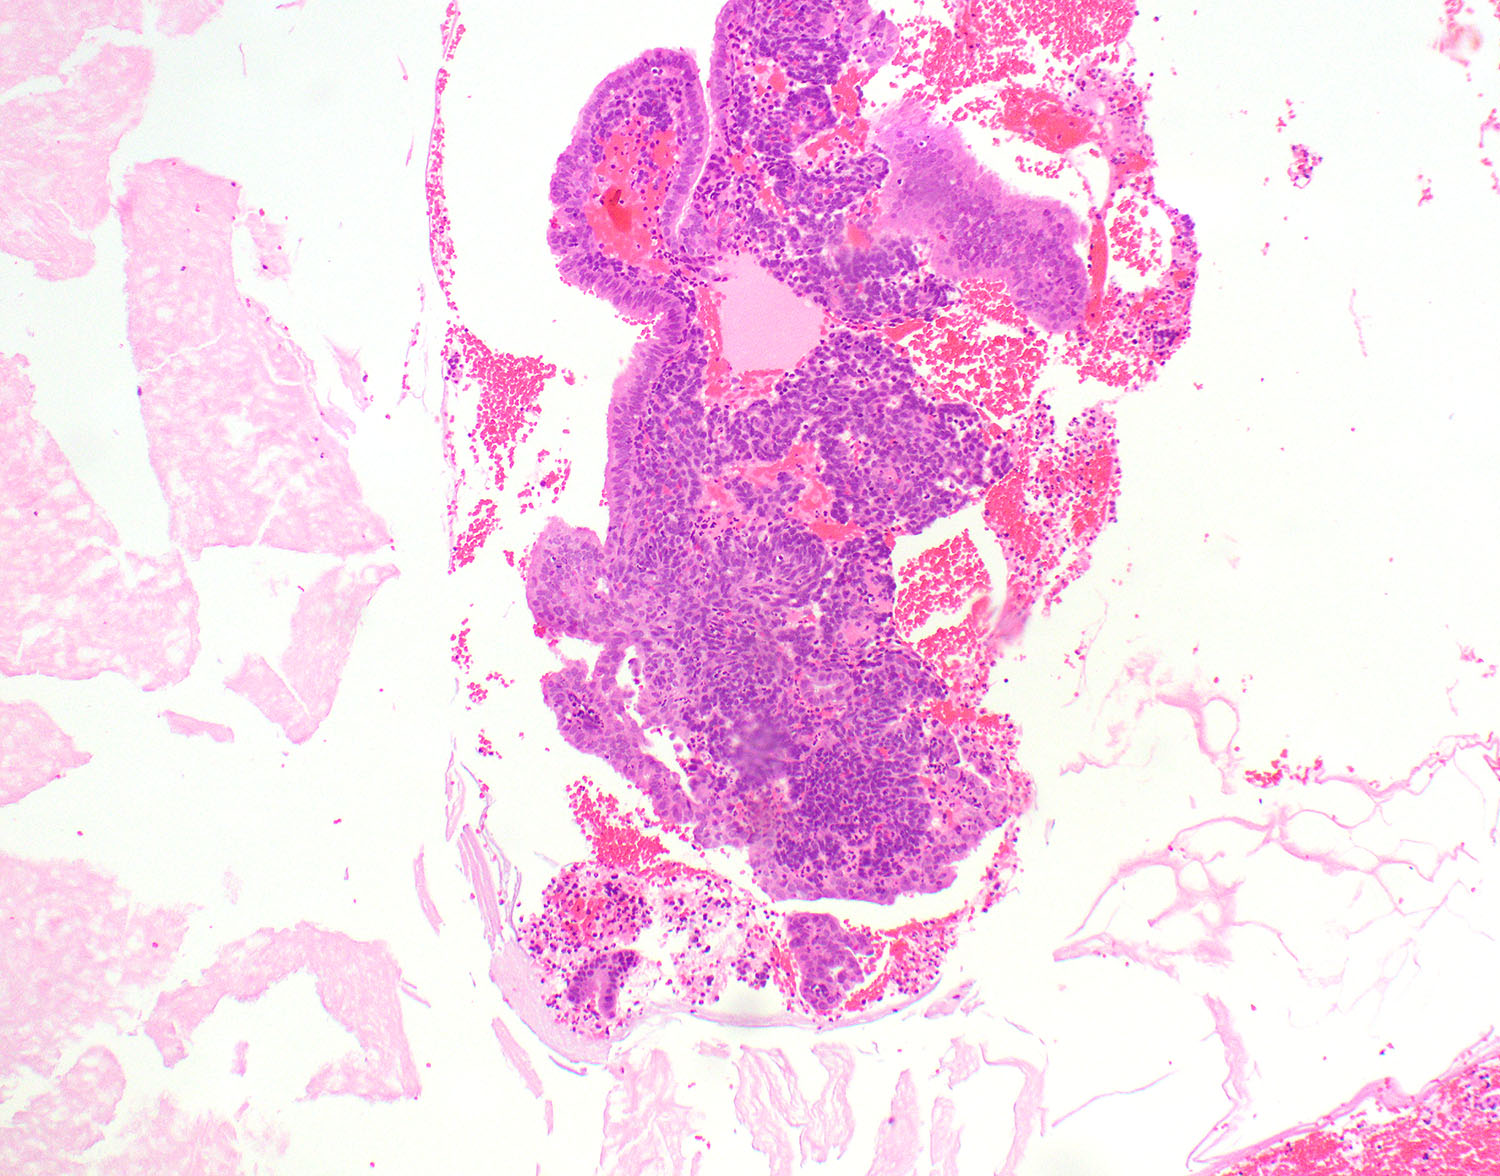

What phase endometrium is pictured in the image?

Practice answer #1

D. Secretory phase. The endometrial glands are lined by a single layer of low columnar cells with pink cytoplasm and prominent glandular secretions. There is predecidual change in the stroma.

Practice question #2

The pictured endometrial sample was most likely obtained from which of the following patients?

Practice answer #2

C. Pregnant woman. The image shows an example of gestational endometrium. There is decidual change in the stroma with abundant eosinophilic cytoplasm and polygonal cells with prominent cell borders. The glandular cells show Arias-Stella reaction.